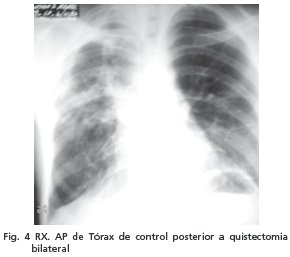

En la segunda intervención agosto de 2006 se realizó toracotomía con quistectomía izquierda y cierre de fístulas broncopleurales, con extracción del quiste en su totalidad, de 25 cm de diámetro. En el postoperatorio en la unidad de terapia intensiva, en las 2 oportunidades no presentó ninguna intercurrencia. Se tomaron las placas radiológicas de control y fue externado sin complicaciones, teniendo su control a los 2 meses (fig. 4 ).